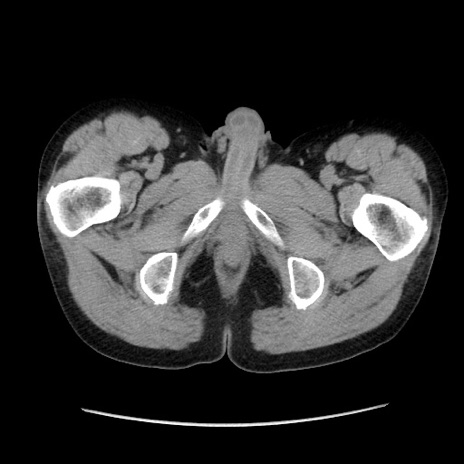

症例37(横断像)

【症例】40歳代 男性

【主訴】腹痛

【現病歴】4時間ほど前に電車に乗車中に臍部上より腹痛出現。徐々に増悪し起立困難となり、救急外来受診。生ものは数日食べていない。今朝お雑煮を食べた。

【身体所見】BT 36.8℃、BP 117/84mmHg、HR 91/min、SpO2 97%、苦悶様、腹部:臍上部広範囲圧痛あり、反跳痛±

【データ】WBC 8100、CRP 0.03